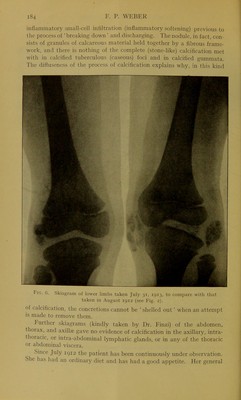

Subcutaneous calcinosis or multiple calcification in the subcutaneous tissue / by F. Parkes Weber.

Credit: Subcutaneous calcinosis or multiple calcification in the subcutaneous tissue / by F. Parkes Weber. Source: Wellcome Collection.